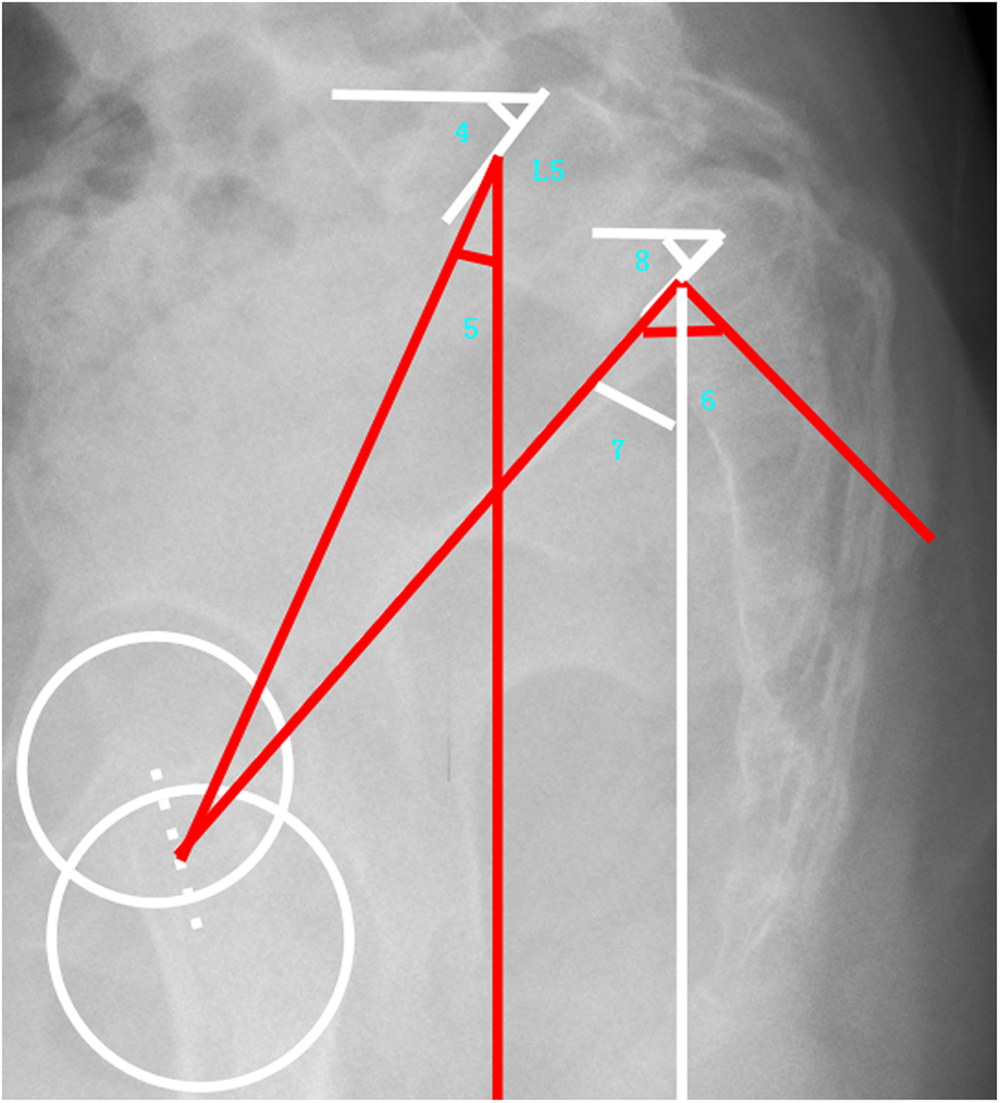

Figure 3

Demonstrated sagittal lumbosacral parameters (4: L5 Slope, 5: L5 Incidence, 6: Pelvic Incidence, 7: Pelvic Tilt, and 8: Sacral Slope).